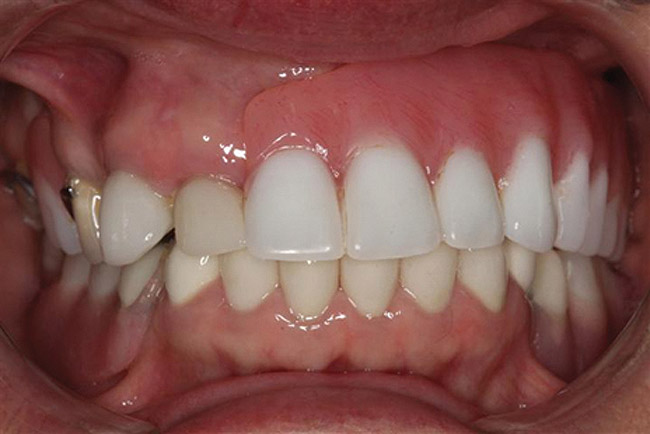

Figure 10  Postoperative images of the patient’s restorative smile.

Figure 10

Figure 11  Postoperative images of the patient’s restorative smile.

Figure 11

Upon delivery, the prosthesis was screwed into the implants and torqued to 15 Ncm. The screw access hole was filled with Impla-plug (Swiss Quality Dental Implant Studio, www.renzoswissquality.com) to within 1 mm of the top of the sleeve. Composite material was then used to bring the screw access hole level with the surface acrylic. The procedure was repeated for the lower denture (Figure 10 and Figure 11).